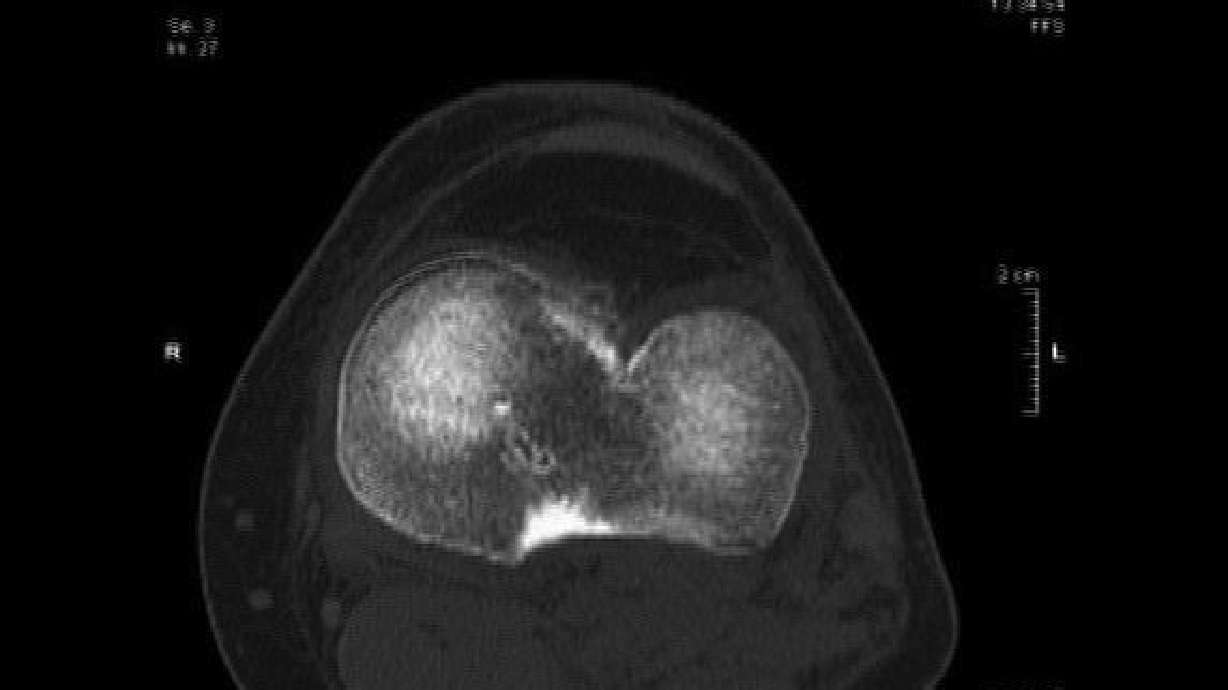

A type of knee injury that's familiar to many athletes may not always require surgery right away. Hi, I'm Dr. Cindy Haines, host of HealthDay TV. Injuries to the anterior cruciate ligament in the knee - also known as the ACL - are most common in young people who are physically active. These injuries can lead people to become less active and have trouble using their knee. ACL tears are commonly repaired with surgery, and more than 200,000 ACL reconstructions are done each year. A new study in the New England Journal of Medicine followed 121 young, active adults with ACL injuries. Some of them began rehabilitation for their knee and also had surgical reconstruction of the ligament soon after the injury. The rest had rehab, but put off surgery until later if necessary. After two years, both groups had similar improvements in pain, symptoms, ability to perform sports and recreational activities, and knee-related quality of life. By reserving the surgery as a later option, more than half of ACL reconstructions might be avoided without compromising results, according to the researchers. But as another expert pointed out in the journal, these injuries should be handled on a case-by-case basis. IÕm Dr. Cindy Haines of HealthDay TV, with the news that doctors are reading; health news that matters to you.